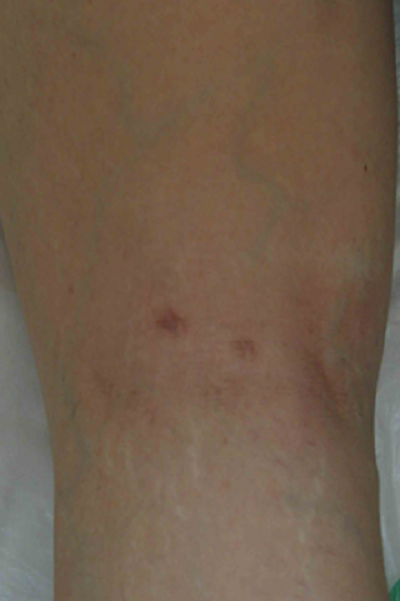

患者,女, 53岁。因“发现左膝肿块2月”入院。体检示左膝腘窝内侧可及4cm*4cm质韧肿块,压痛(-),活动度良好。左膝内侧关节间隙压痛(+),麦氏征(+)。MRI示“左膝腘窝囊肿,左膝内侧半月板损伤”。经完善术前准备后行关节镜治疗术。术中先采用后侧入路,行关节镜下囊肿切除,然后行常规关节镜检查,处理关节腔内半月板损伤,同时经后内侧入路打开腘窝囊肿与关节腔通路。

后路关节镜下切除囊肿,术后次日患者下床活动并出院,术后半年随访显示关节活动良好,未见囊肿复发。